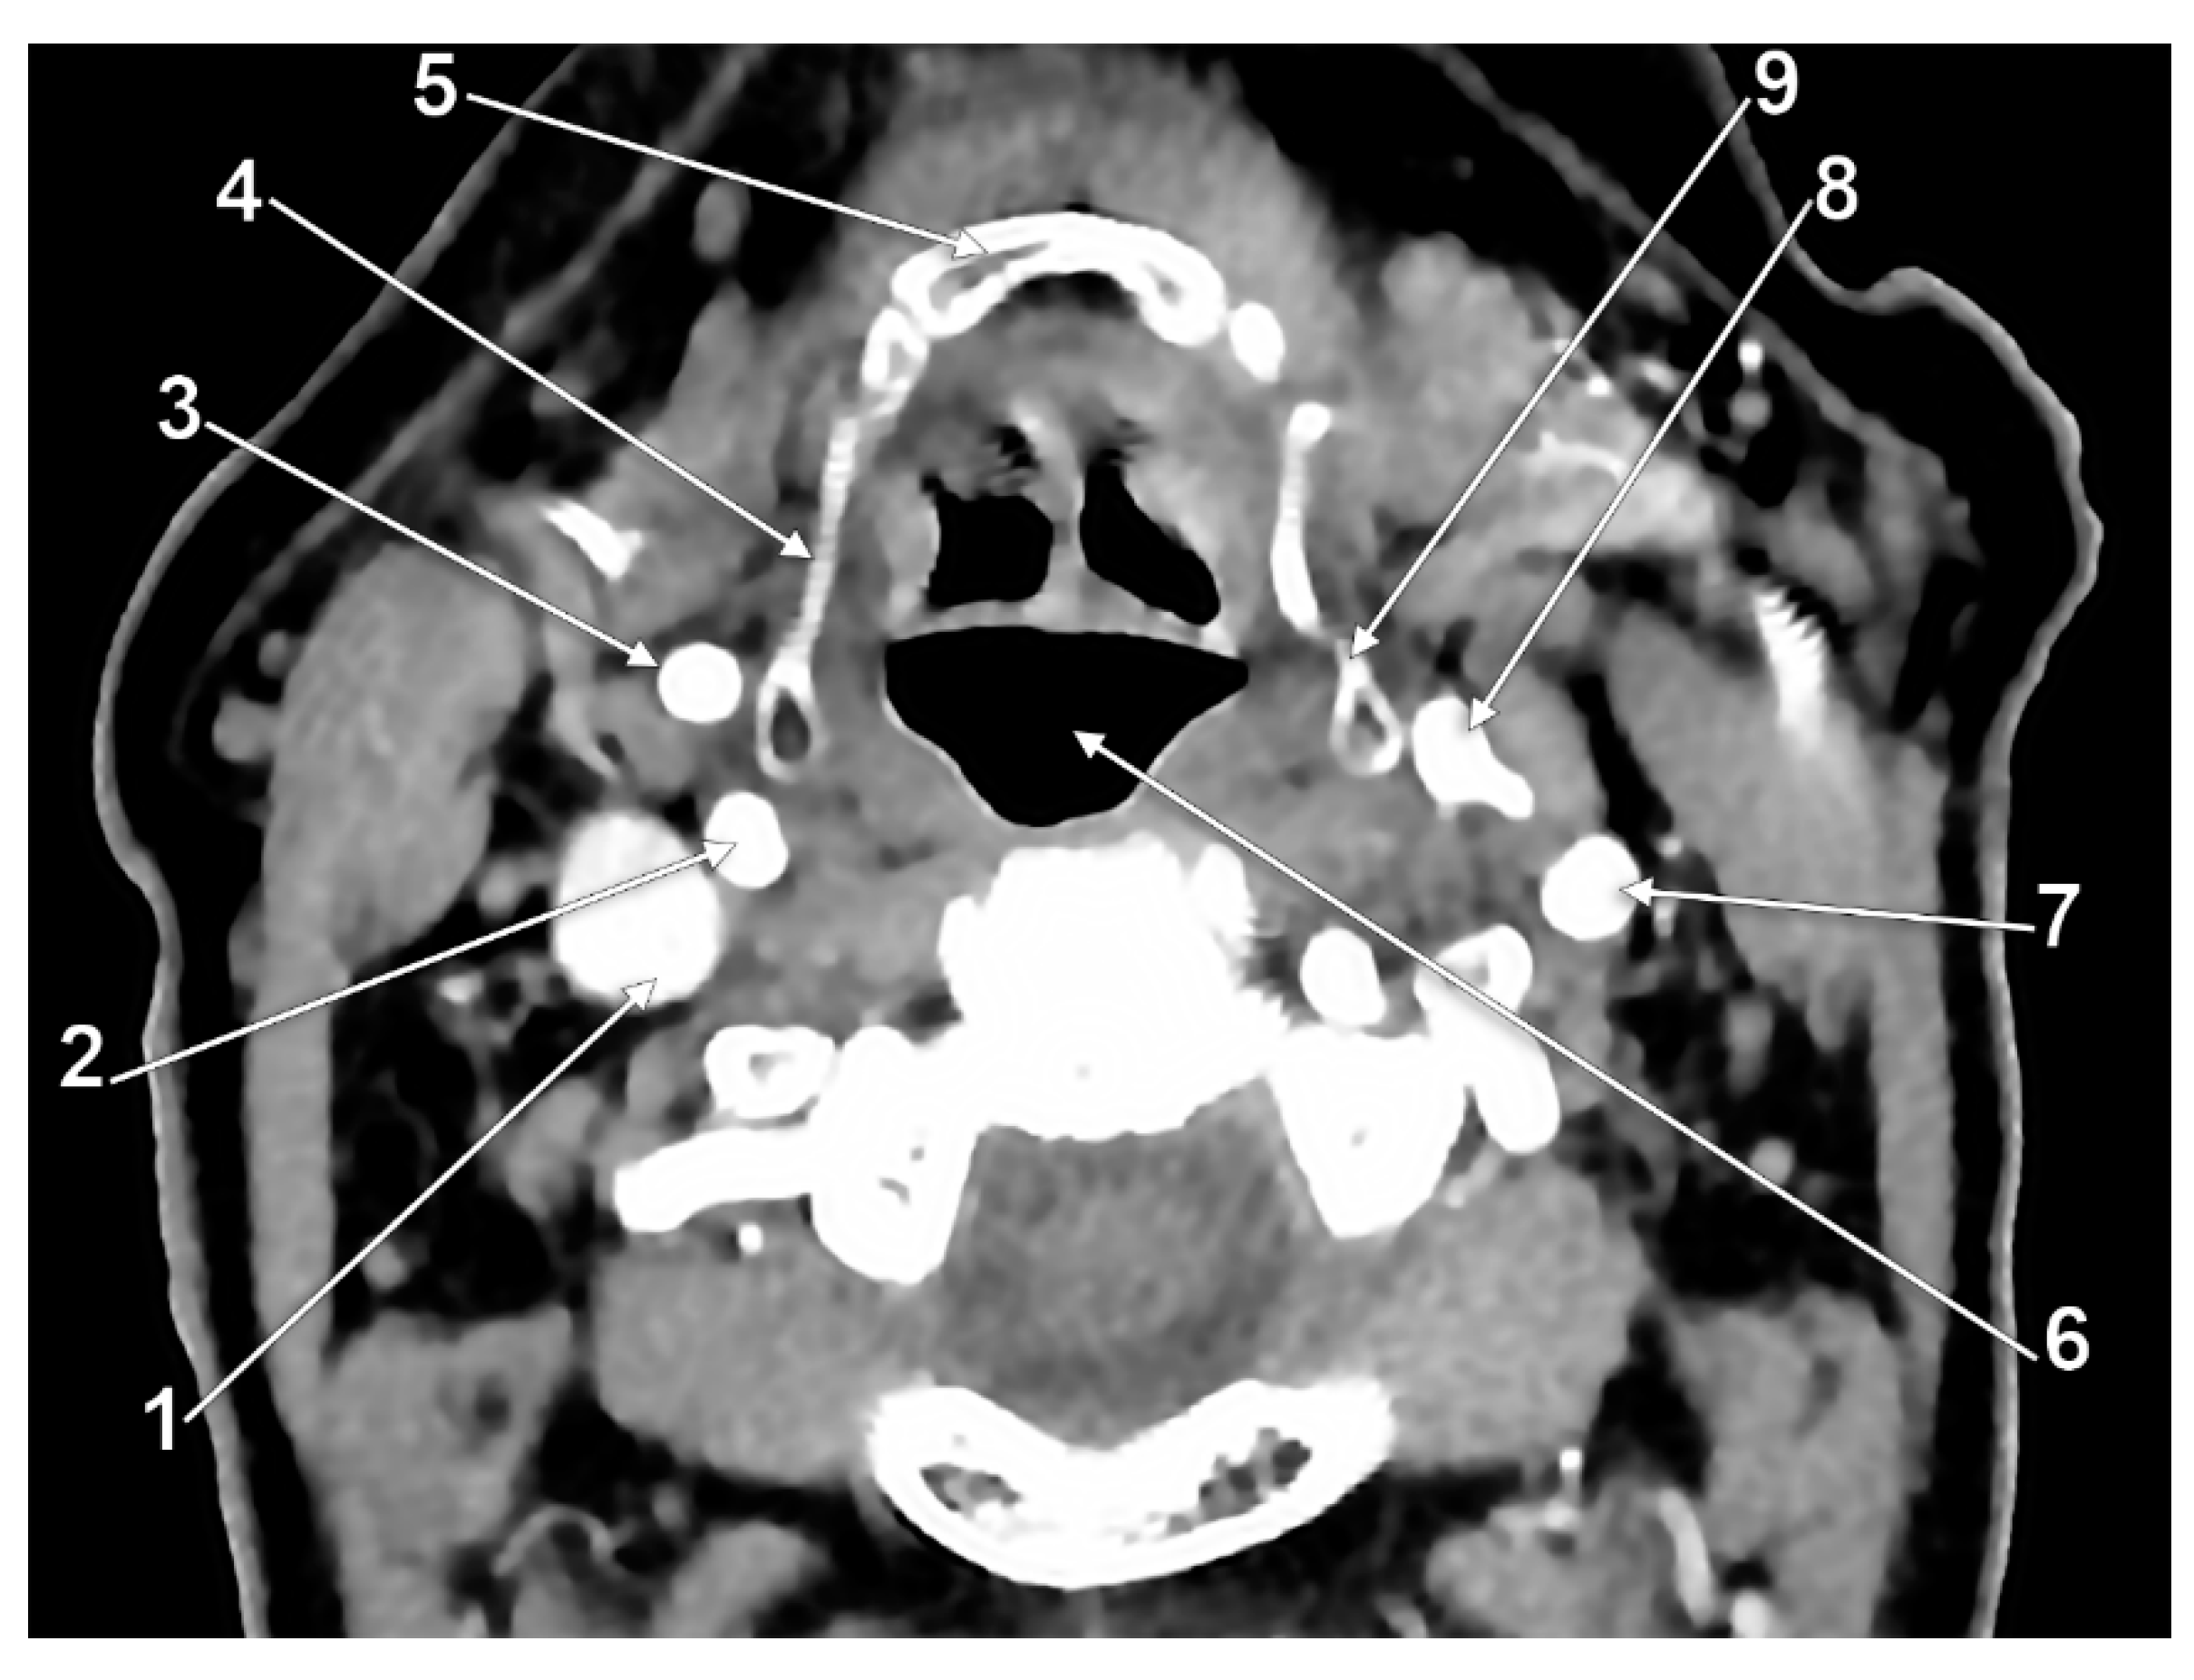

The Carotid–Hyoid Topography Is Variable

Manta, M.D.; Rusu, M.C.; Hostiuc, S.; Vrapciu, A.D.; Manta, B.A.; Jianu, A.M. The Carotid–Hyoid Topography Is Variable. Medicina 2023, 59, 1494. https://doi.org/10.3390/medicina59081494